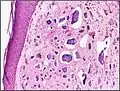

![]() | |

Micrograph of calcinosis cutis. The calcification is purple (bottom of image). H&E stain. | |